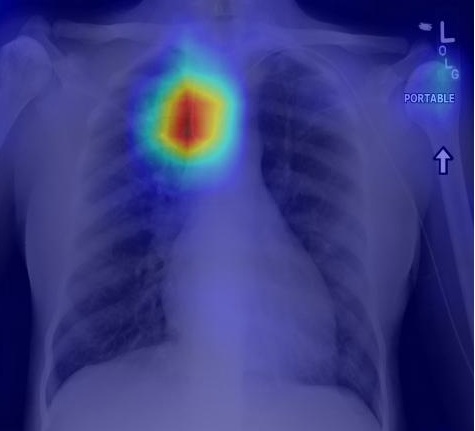

Recognizing normal/abnormal positioning of lines and tubes and their tips with answers derived from the AI attention heat map of a deep learning model

We have developed deep learning AI models trained on chest X-ray images focused on2 stages: (i) segmentation and (ii) classification of lines and tubes. A segmentation model generates masks for any lines and tubes present on a CXR image, which will then be fed to the classification model for identification of the type of line and the position of the tip.

Performance results for central venous catheter (CVC) and endotracheal tube (ETT) tip localisation:

A5 - fold cross-validation of the model was conducted using 5,867 images. The results showed that the classification model can accurately identify the position of the  tip as normal or abnormal, with an area-under-curve (AUC) of 0.902 for central venous catheters and 0.959 for endotracheal tubes.